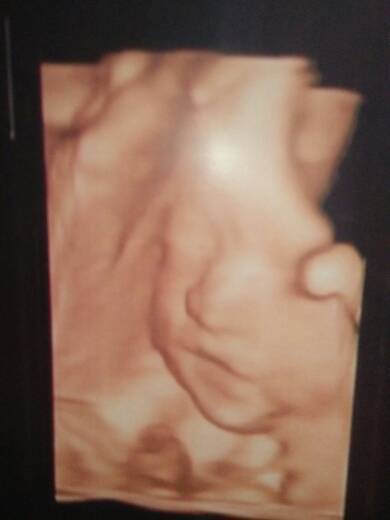

我今天去做了四维B超,好开心啊,看到宝宝那么可爱,蛮喜欢的,特别是宝宝的那小嘴巴好可爱呀!超级喜欢

我今天去做了四维B超,好开心啊,看到宝宝那么可爱,蛮喜欢的,特别是宝宝的那小嘴巴好可爱呀!超级喜欢!宝宝妈妈爱你!